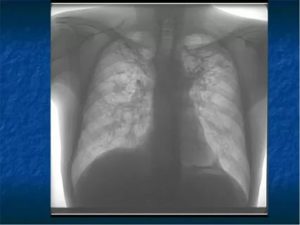

Для визуализации патологического процесса назначается рентгенологическое исследование органов грудной клетки, которое позволяет обнаружить изменения в легких. Обнаруживаются изменения с обеих сторон, преимущественно в нижних отделах легких.

Отмечаются усиление и деформация легочного рисунка, постепенно формируется картина так называемого «сотового легкого», которое характеризуется образованием кольцевых теней диаметром 3 – 7 мм со стенками толщиной до 3 мм, что в некоторой мере напоминает пчелиные соты.